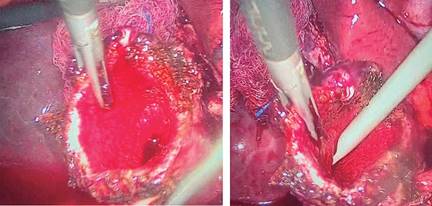

3. Hacer una ligadura del remanente vesicular con un endoloop, el cual se realiza de forma manual con sutura de Vicryl® del calibre 2-0, procurando que la ligadura quede a nivel de donde se pudo visualizar el conducto cístico (Figura 3).

4. Corroborar un adecuado cierre del remanente vesicular, se procede a hacer resección del tejido que queda por arriba de la ligadura para posteriormente realizar una mucoclasia con energía monopolar utilizando el modo spray (40 watts) (Figura 4).